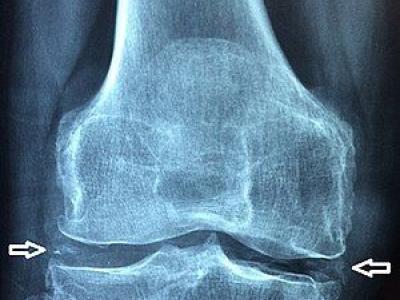

Is the nosology of CPPD outdated? Pseudogout to chondrocalcinosis? In 2011 EULAR taskforce rec the preferred term "calci

Is the nosology of CPPD outdated? Pseudogout to chondrocalcinosis? In 2011 EULAR taskforce rec the preferred term "calcium pyrophosphate deposition dz". G-CAN aims to update & standardised terminology for CPPD, requiring change to ICD-10 & adoption by societies https://t.co/wTdc0Tosc6